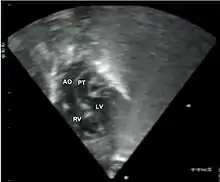

•Echocardiogram: An echocardiogram is an ultrasound of the heart that accurately assesses the heart’s structure and function, and can show the specific features of TGA, if present. This imaging modality allows for the definitive diagnosis of TGA to be made.[3]

Abbreviations: LV and RV=left and right ventricle, PT=pulmonary trunk, VSD=ventricular septal defect, PS=pulmonary stenosis.